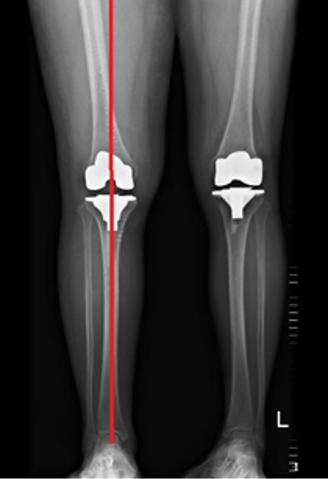

术后X片

髋-膝-踝角180°(理想值180°)

手术完美恢复下肢力线

术前双下肢全长X片

髋-膝-踝角169°

(内翻11°)